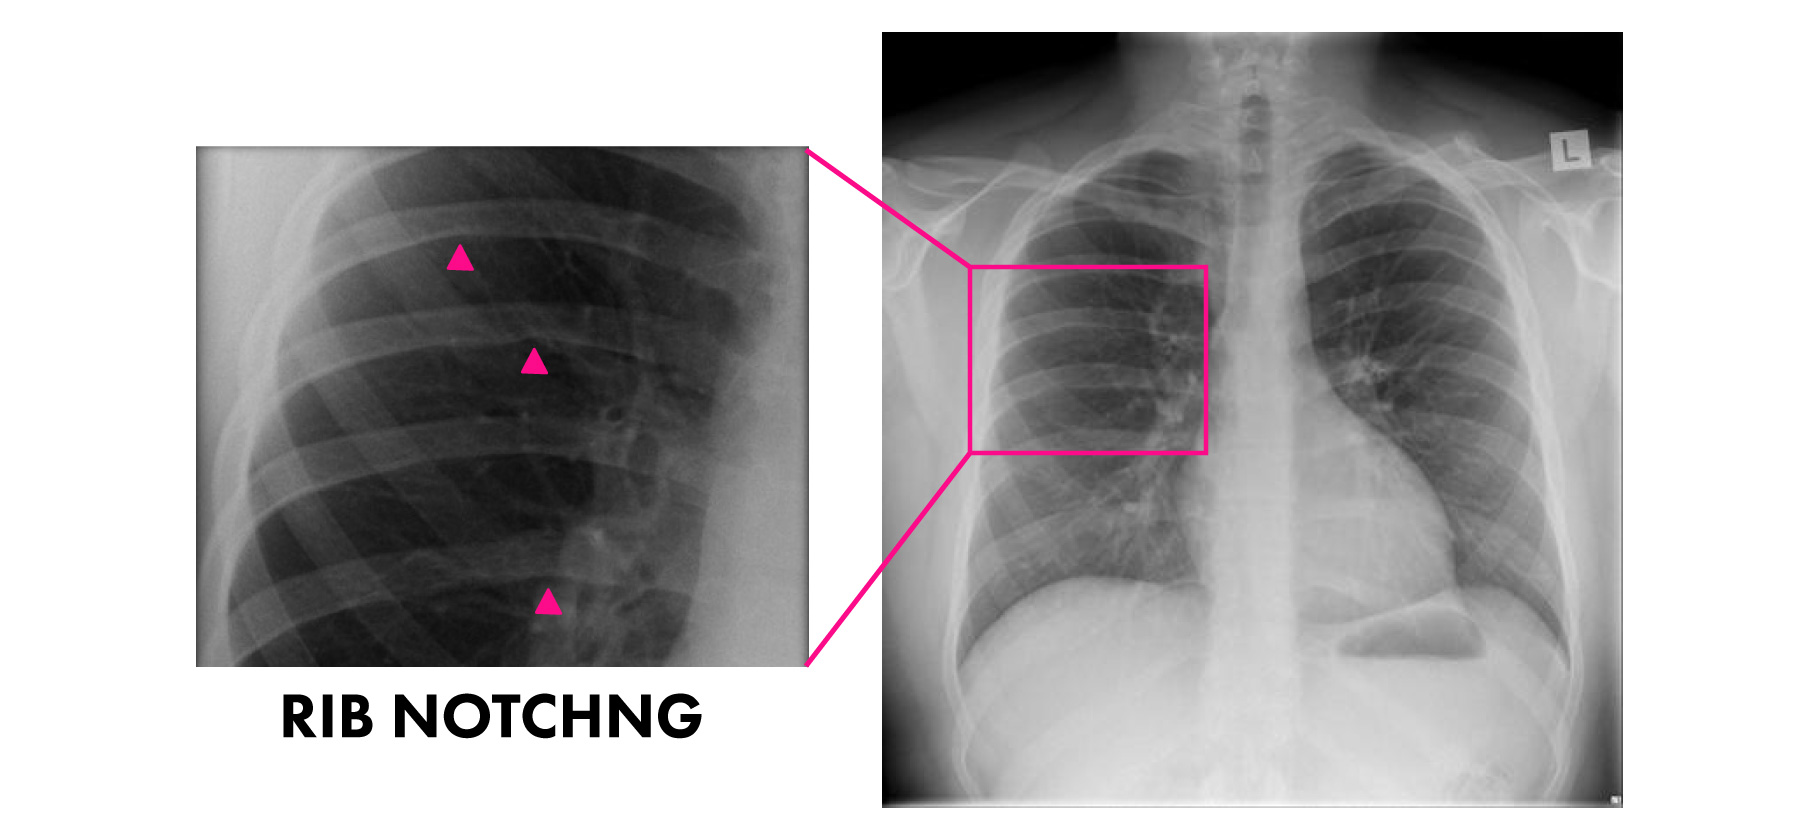

Inferior Rib Notching causes Note Figure of 3 sign & Inferior rib Rib Notching Definition Normal variants and abnormalities of the ribs are frequently encountered on chest radiographs. Acute rib infections are seen as focal areas of bone destruction, whereas chronic infections may manifest as periosteal reaction or a bone sequestrum. This article discusses how ribs are involved in a variety of traumatic, metabolic, inflammatory, neoplastic, and congenital disorders. Rib notching are deformities that affect. Rib Notching Definition.

Inferior rib notching remodeling deformity of the lower aspect of the Rib Notching Definition Rib notching are deformities that affect the upper surface of the rib, the lower surface of the rib (roesler’s sign), or both. Acute rib infections are seen as focal areas of bone destruction, whereas chronic infections may manifest as periosteal reaction or a bone sequestrum. This article discusses how ribs are involved in a variety of traumatic, metabolic, inflammatory, neoplastic,. Rib Notching Definition.

Rib Notching Epomedicine Rib Notching Definition Normal variants and abnormalities of the ribs are frequently encountered on chest radiographs. Acute rib infections are seen as focal areas of bone destruction, whereas chronic infections may manifest as periosteal reaction or a bone sequestrum. Rib notching are deformities that affect the upper surface of the rib, the lower surface of the rib (roesler’s sign), or both. This article. Rib Notching Definition.